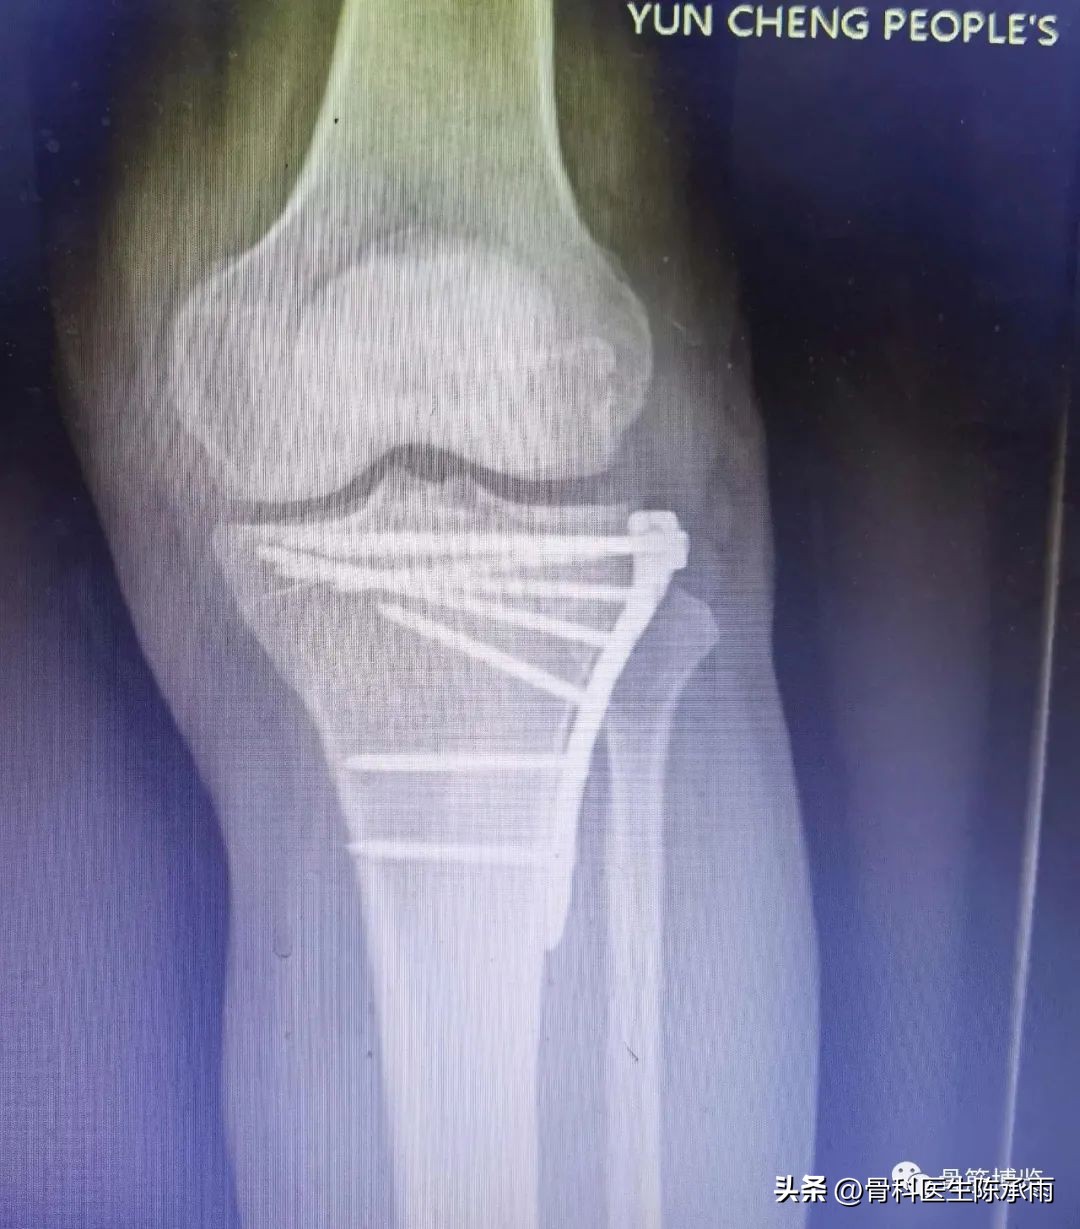

1例

2例

3例

4例

5例

6例

7例